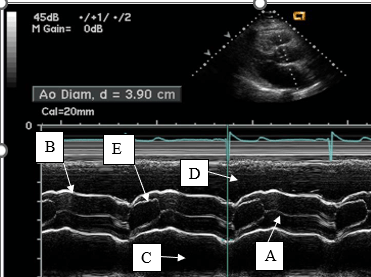

Letter E represents this aortic valve cusp and it's position during systole.

What is the right coronary cusp in the open position?

This line represents aortic valve closure on m-mode.

What is A?

Letters A and C represent these waveforms.

What is a- rapid or early filling and c - atrial systole or atrial kick?